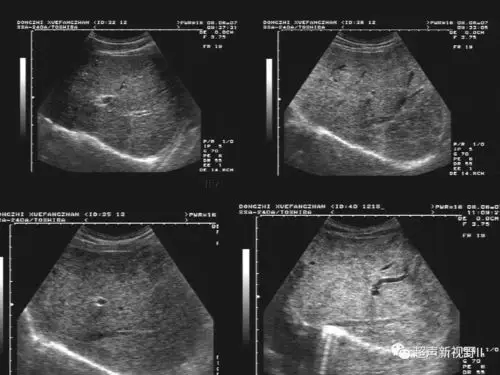

几张成人腹部超声图片

腹腔干和肠系膜动脉

多年腹痛:超声发现病因竟然是一根血管